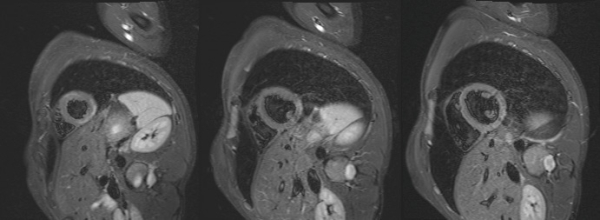

Figure 2 : Séquence T2 STIR, coupes petit-axe

Figure 3 : Séquence T2-mapping, coupes petit-axe

Cinétique du VG normale mais présence d’une prise de contraste sous-épicardique diffuse.

Myocardite aiguë étendue à la paroi inféro-latérale et latérale débordant en septo-apical.

- La topographie sous-épicardique du réhaussement tardif est très en faveur d’une pathologie inflammatoire évocatrice de myocardite.

- La présence de l’œdème myocardique sur les séquences de T2-STIR et T2 mapping traduit un phénomène inflammatoire récent dans les 4 dernières semaines.